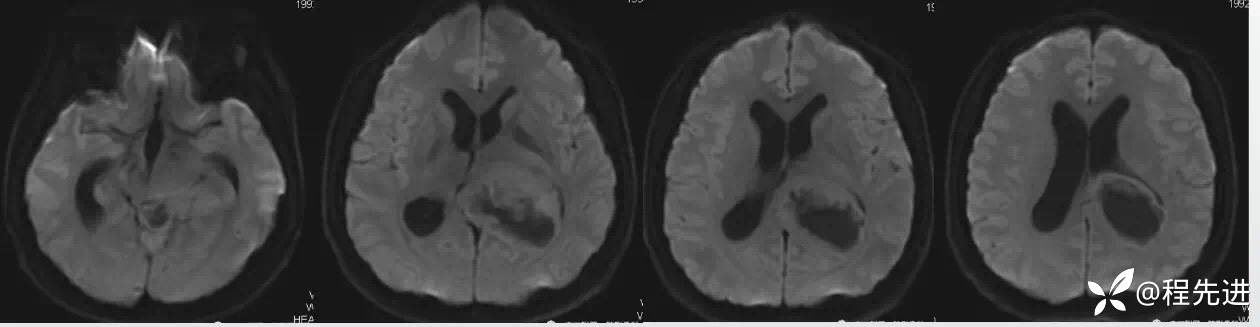

DWI:

FLAIR: